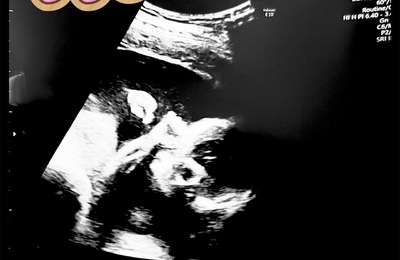

みなさんこんにちは! くまです🐻 先日20週のスクリーニング検査があったので、 そのレポを書きたいと思います^^ 妊娠20週前後、30週前後でスクリーニング検査があります⭐️ スクリーニング検査とは、赤ちゃんの先天性異常や染色体異常を詳しくみる検査です! 私の通う山王病院ではエコー検査でした! 30分ほどエコーで赤ちゃんを確認するので、 長い時間赤ちゃんを見ることができて嬉しい時間でした🍼 検査で…